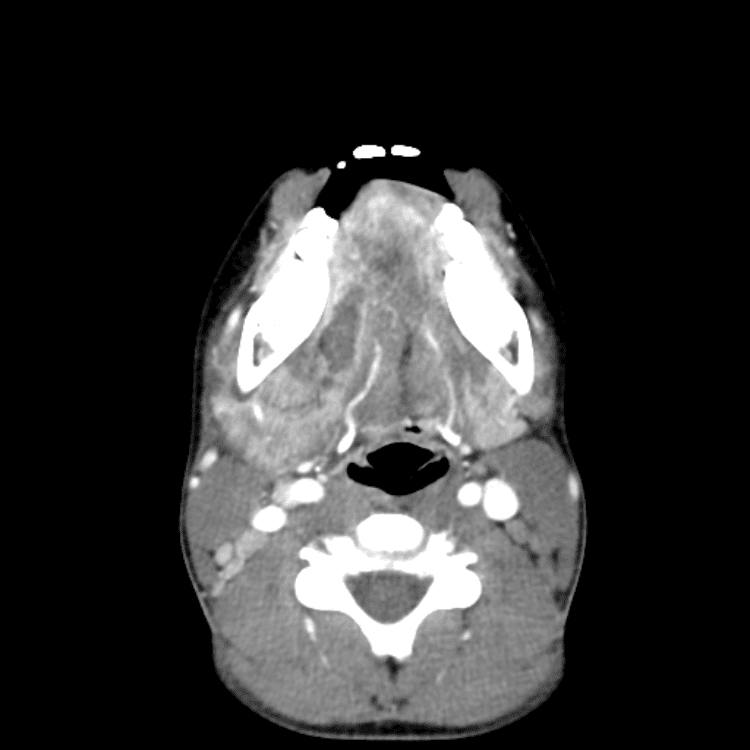

Head and Neck

Practice

Simulates call by including subtle or difficult cases and some normals.

27 cases